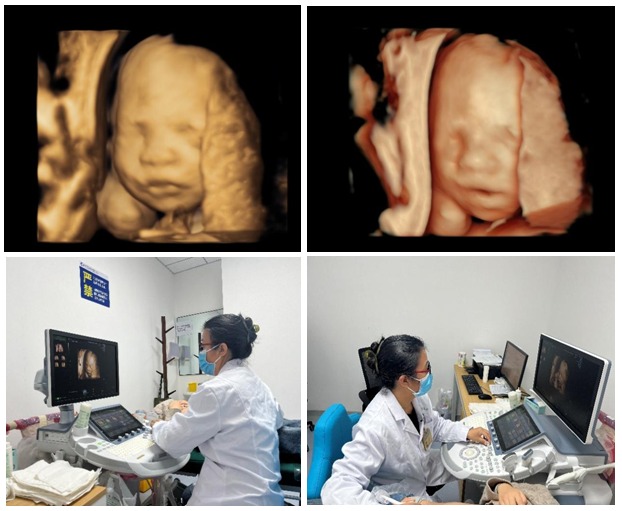

10月30日,21点技巧中心 超声诊断中心西咸院区开展第一例胎儿心脏彩色多普勒超声检查,同时开展了超声诊断中心西咸院区第二例输卵管超声造影。

10月31日,超声诊断中心西咸院区为一位29岁的二胎孕妇,成功开展胎儿四维系统彩色多普勒超声检查,这是西咸院区的第一例胎儿四维系统超声检查。